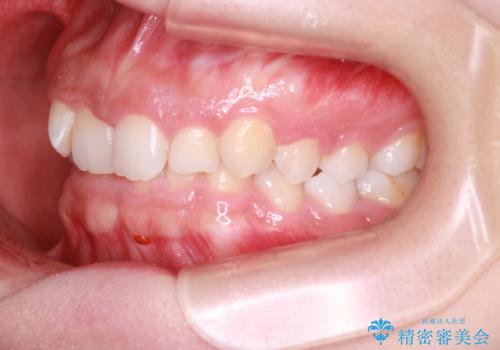

インビザラインで整える深い噛み合わせ

- 患者様は、ディープバイト(深い噛み合わせ)と、咬合平面の左下がりが気になるとのことでご来院されました。診断の結果、非抜歯で治療可能と判断し、透明なマウスピース型矯正装置「インビザライン」を用いる方針としました。治療では、歯列全体の調整を行いながら、咬合平面の水平化を重点的に進める計画を立案しました。2年間で計画的にマウスピースを交換し、左右のバランスと噛み合わせの改善を目指しました。

ディープバイトの矯正は、噛み合わせが深くなりがちなため、細心の注意を払いながら進める必要があります。本症例では、奥歯の高さを調整しつつ前歯の噛み合わせを浅くすることで、全体の咬合バランスを整えました。また、咬合平面の左下がりを修正する過程で、歯列に不均等な力がかからないよう、インビザラインのアタッチメント配置を最適化しました。患者様には装着時間を守っていただき、治療が計画通り進むよう協力をお願いしました。治療終了後には、リテーナーを装着して安定性を確保しました。